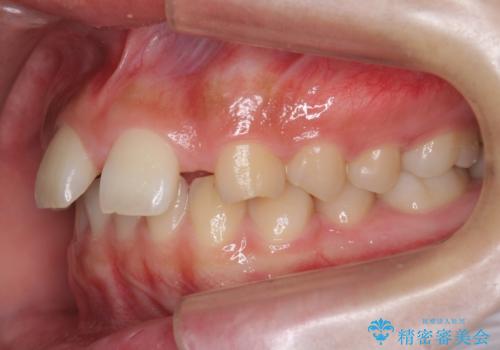

また、右の奥歯の関係も上が前にある状態で大きくずれていました。

臼歯関係は無理に1級にしようとすると抜歯が必要になります。

今回は左右とも1歯対2歯の関係であるため、それは変えずに前歯を可及的にひっこめて足りない部分をブリッジで補う治療としました。

奥歯の関係を完全に1級にするには右上の小臼歯の抜歯が必要でしたが、もともと左上の前歯が生まれつき少ないため今回は歯を抜かずに治療しています。